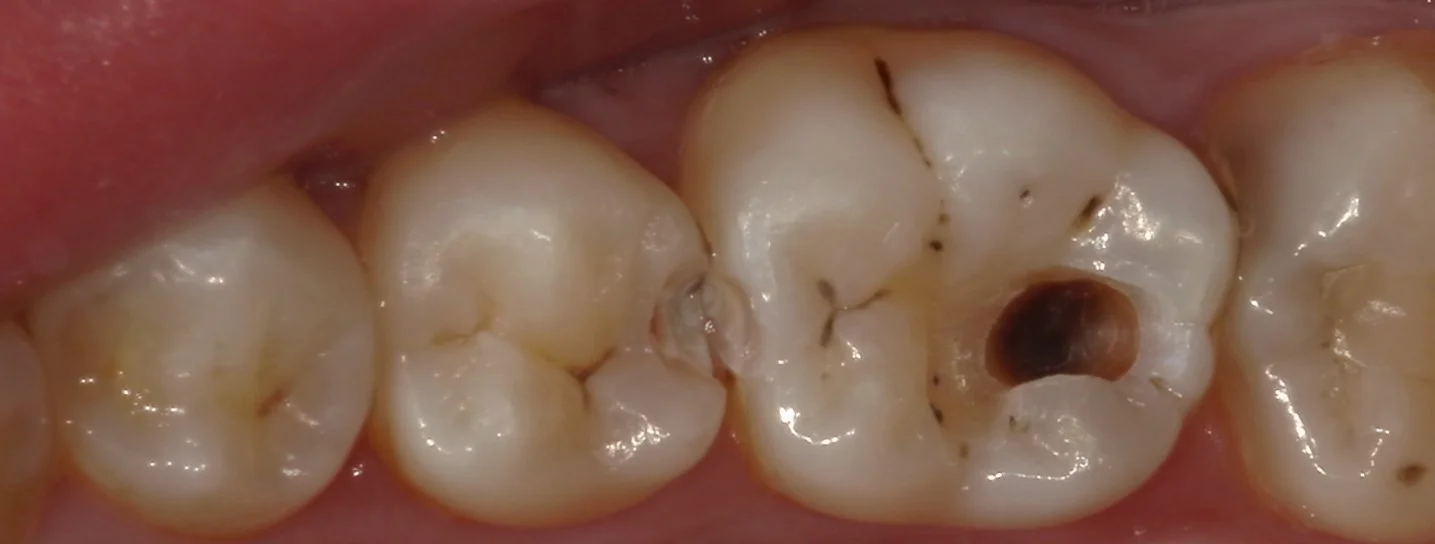

さて、では術前から。

どこが虫歯が変わりますかね?

1か所はあからさまに黒いのが透けているので分かりやすいかもしれませんね。

軽く削って、虫歯が見えやすくなった状態がこちら。

どうです?

結構黒いのが分かりやすくなりましたよね?

また、手前の歯との間にも黒い部分があるのが分かるかと思います。

削っているので分かると思いますがもちろんここも虫歯です。

上の術前の写真では非常に分かりづらく、拡大鏡で覗いても油断すると見逃してしまいそうな状況でした。